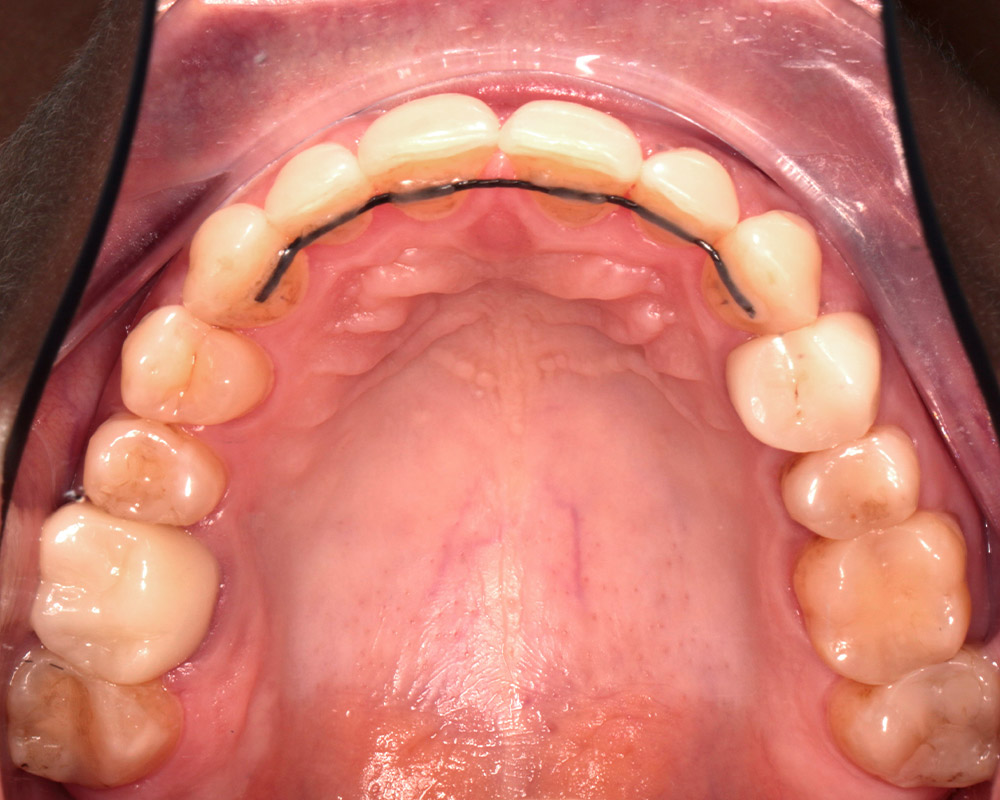

Кейс 21

ДО

ПОСЛЕ